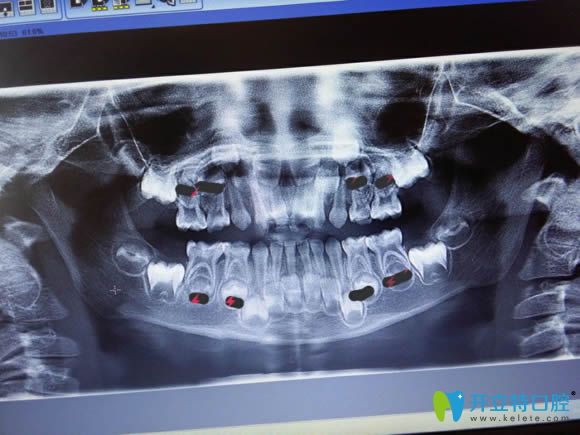

兒童牙片顯示圖

牙齒的X線片俗稱牙片,是牙醫(yī)診療的重要工具之一。通過(guò)牙片,可以了解到蛀牙的范圍,以及牙周炎癥的病變程度,還有成人年種植牙所需要的骨量、某些腫瘤等等??梢詭椭t(yī)生發(fā)現(xiàn)病變并確定其程度、范圍及治療深度,治療后也便于觀察療效。

牙片主要有全景片(大片)和根尖片(小片)兩種類型。